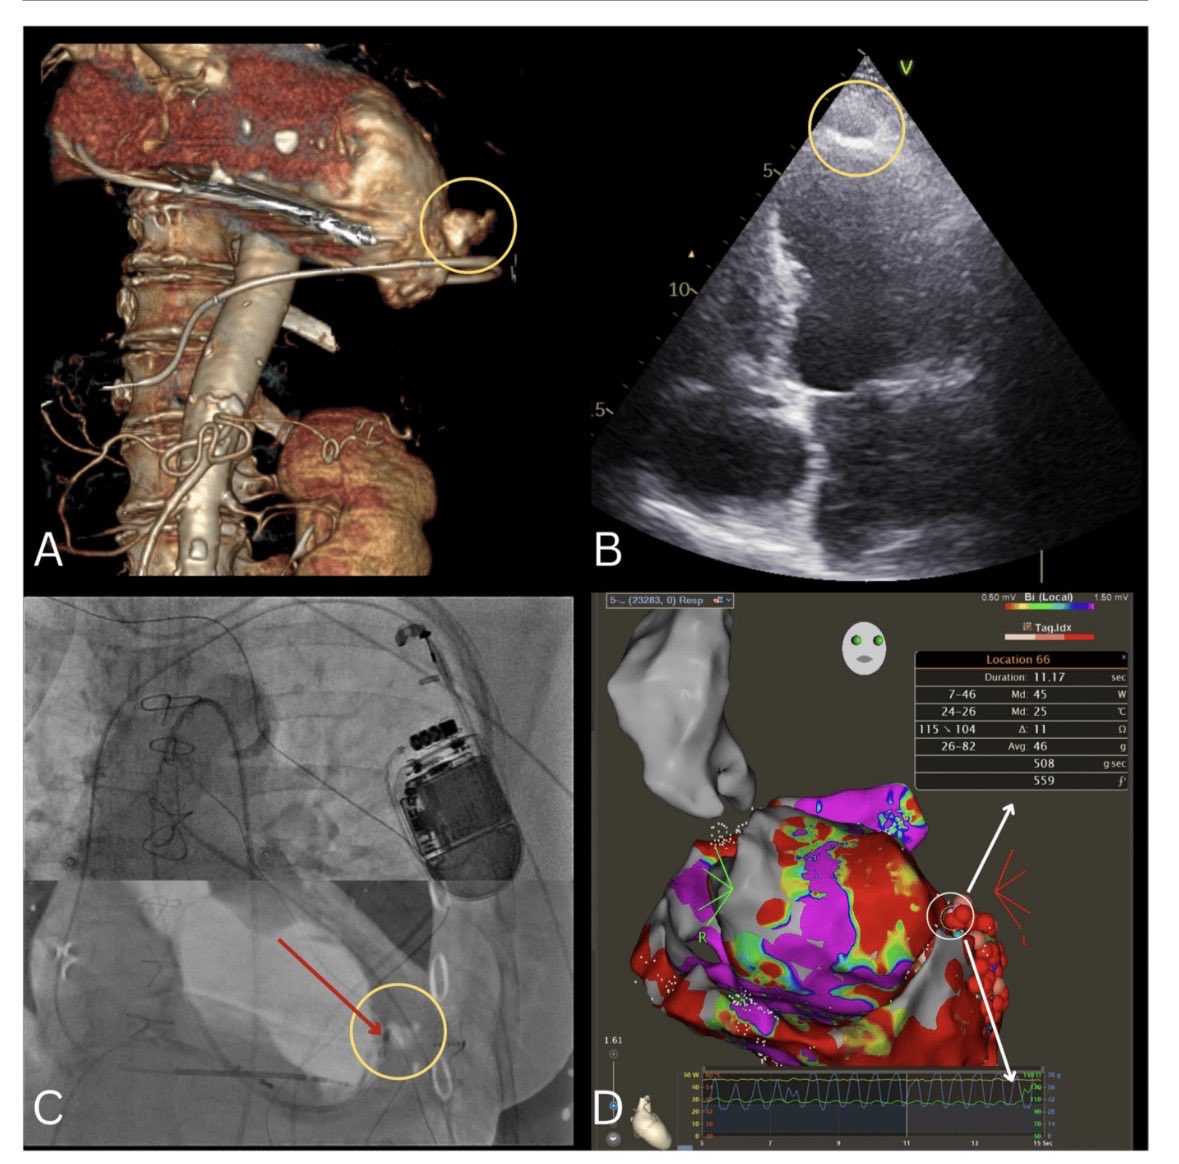

Newest publication in @JICE_EP from our @EP_WSS - Intramural hematoma as a rare complication of endo-epicardial VT ablation https://t.co/WW6OtriCcg #ablateVT #EPeeps